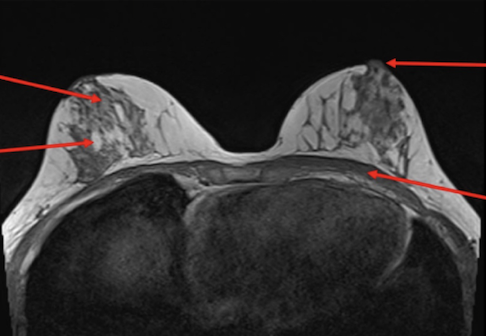

What are the sequences and what is the pathology?

• T1, STIR, T1FS C+

• Tissue lipoma- benign tumour made of fat tissue